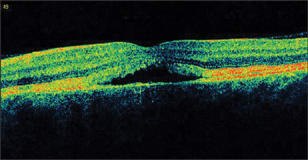

Optical coherence tomography (OCT) scans showed a well-defined material accumulation underneath the RPE in the right eye, with more pronounced cystic changes in the left eye (Figure 2).

Figure 2. OCT images of both eyes showing a subretinal pigment epithelium conical mound of moderately reflective material in the right eye (left scan) and a larger cystic space in the left eye (right scan).